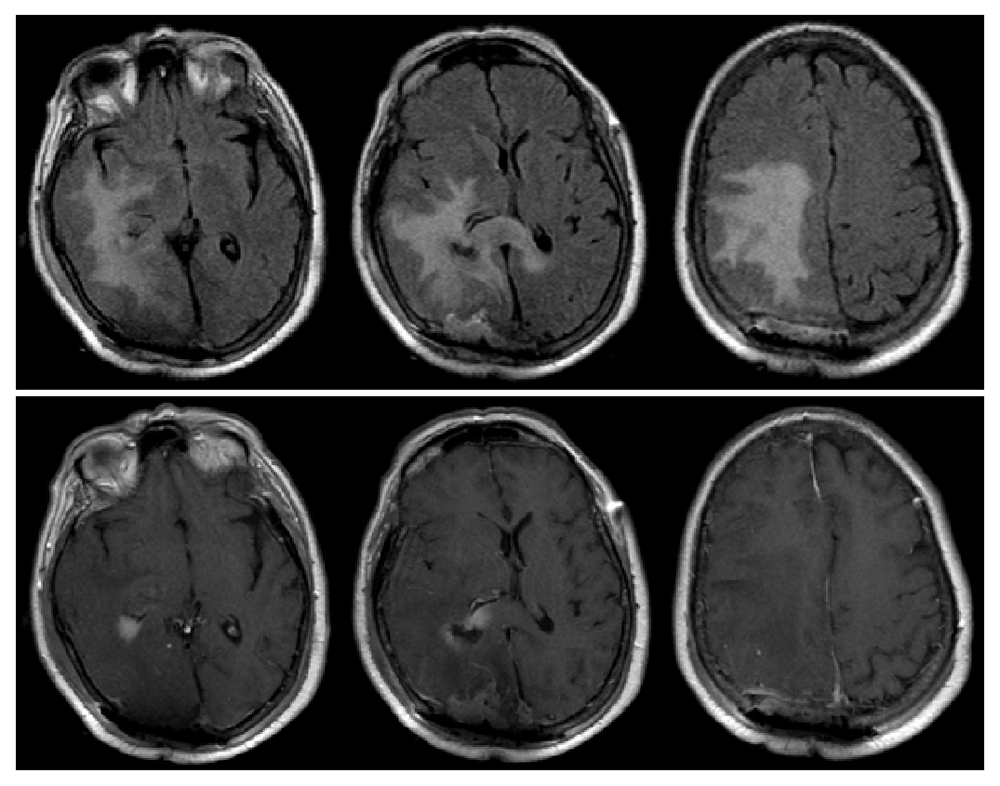

After preoperative clearance, a right occipital craniotomy was performed with anticipation for gross total resection of the right parieto-occipital lesion and biopsy with likely subtotal resection and biopsy of the second lesion. Preliminary pathology from intra-operative frozen specimen were consistent with meningioma (extra-axial lesion) and high-grade glioma (periventricular lesion). Gross total resection was performed for the extra-axial lesion and maximal, safe resection of the periventricular lesion was performed. She tolerated the procedure well and had an improved neurological exam postoperatively. Her left hemiparesis improved compared with pre-operative exam, however, she did have very minor left visual field deficits. Post-operative MRI demonstrated gross total resection of meningioma and subtotal resection of what was later confirmed to be diffuse large B-cell lymphoma (Figure 3). During this same admission, she also underwent open reduction, internal fixation (ORIF) of her left bimalleolar fracture without complication. She was discharged home in stable condition.

T1-post contrast reveals gross-total resection of the previously seen extra-axial lesion in the right parieto-occipital region as well as subtotal resection of right periventricular lesion (bottom). The midline shift is significantly improved from pre-operative MRI (Figure 2).